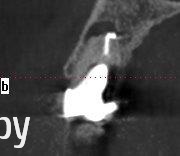

Таня-К Опубликовано 21 июня, 2014 Поделиться Опубликовано 21 июня, 2014 Уважаемые врачи, помогите, пожалуста, с выбором метода лечения 15 зуба.В разных клиниках предложены такие решения:1. Снятие коронки, удаление штифтовой конструкции, ревизия двоканального зуба,озонирование каналов перед пломбированием, пломба, временная коронка, постоянная коронка.2. Резекция верхушки корня с ретроградным пломбированием, костная пластика альвеолярного отростка.3. Удаление и имплантация.Какой метод лечения Вы считаете оптимальным с медицинской точки зрения?Большое спасибо всем. Ссылка на комментарий

Bier Опубликовано 22 июня, 2014 Поделиться Опубликовано 22 июня, 2014 если нёбно кариес корня, то удалять, если корень целый, то РВК с ретроградкой. Ссылка на комментарий